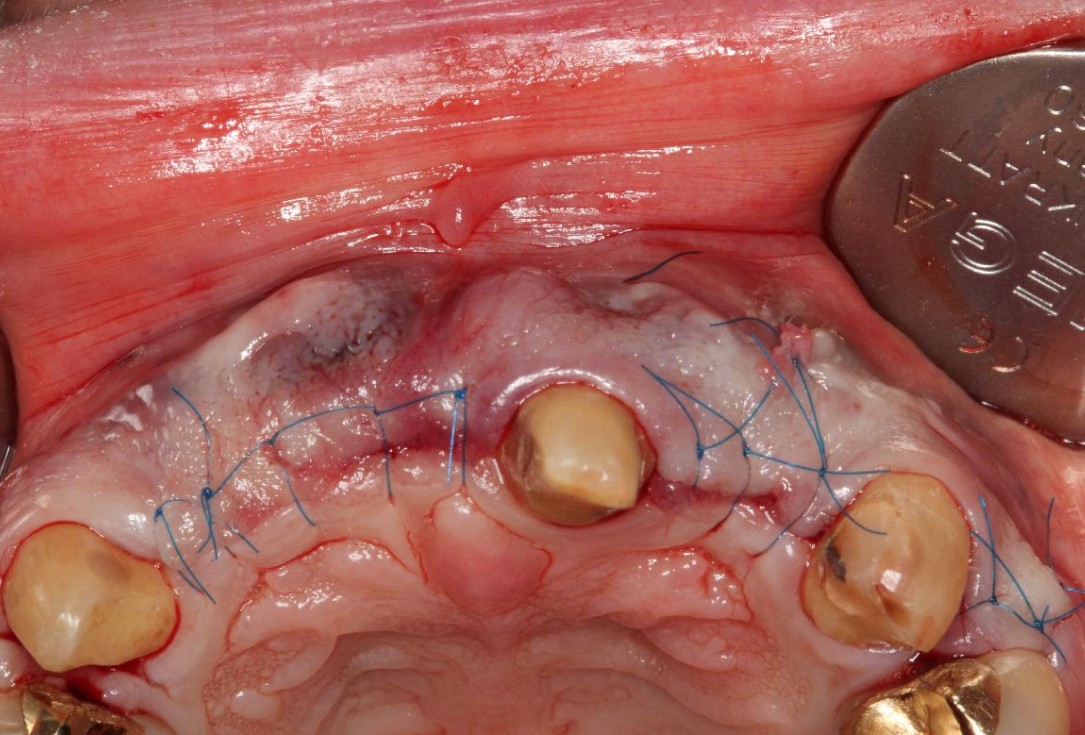

4/5 - Tension-free wound closurePre-prosthetic soft tissue augmentation of the ridge contour with mucoderm®- Dr. F. Rathe